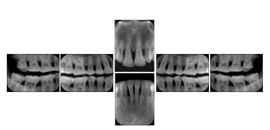

Intra-oral radiography typically involves acquisition of multiple images of various parts of the dentition. Many digital radiographic systems offer customized templates that are used for displaying the images in a study on the screen. These templates may also be referred to as mounts or view sets. The Structured Display Object represents a standard method of encoding and exchanging the layout and intended display of Structured Displays. A structured display object created in this manner could be stored with a study and exchanged with images to allow for complete reproduction of the original exam.

1. A patient visits a General Dentist where a Full Mouth Series Exam with 18 images is acquired. The dentist observes severe bone loss and refers the patient to a Periodontist. The 18 images from the Full Mouth Series along with a Structured Display are copied to a DICOM Interchange CD and sent with the patient to see the specialist. The Periodontist uses the CD to open the exam in his Dental Radiographic Software and consults via phone with the General Dentist. Both are able to observe the same exam showing the images on each user's display using the exact same layout.

Intra-oral Full Mouth Series Structured Display

Figure OO-1. Intra-oral Full Mouth Series Structured Display